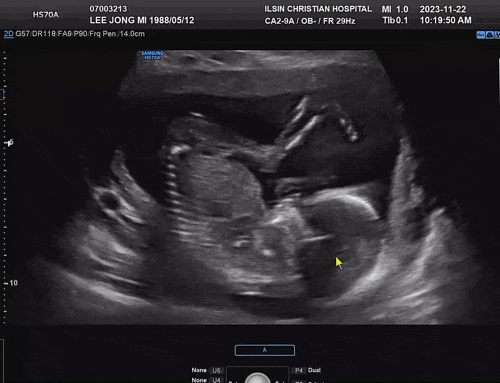

임신29주 - 정밀입체초음파, 시그바리스압박스타킹 구입

안녕하세요. 29주가 되어 정밀초음파 볼겸 병원에 다녀왔어요. 맘카페보니 26주쯤으로해서 다들 찍으시던데...